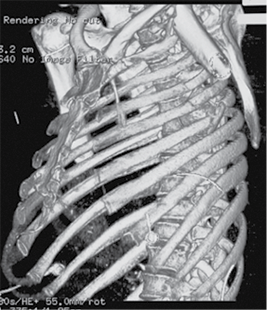

A 58-year-old patient was admitted to the Emergency Department of level I Trauma Center in August 2022 due to polytrauma sustained in a car accident. On arrival, the patient’s condition was severe, with decreased consciousness (GCS score of 12), unstable hemodynamic, subcompensated peripheral circulation, blood pressure of 62/32, and heart rate of 78 beats per minute. There was reduced breathing on the left side with a respiratory rate of 18 breaths per minute and an oxygen saturation (SpO2) of 85.0%. Palpation revealed pain in the left posterior chest. X-rays and CT scans were performed, which revealed a traumatic hemothorax on the left side, humeral head within the pleural cavity, three rib fractures, lung contusion, and hematoma.

Figure 2. Subsequent 3D reconstruction